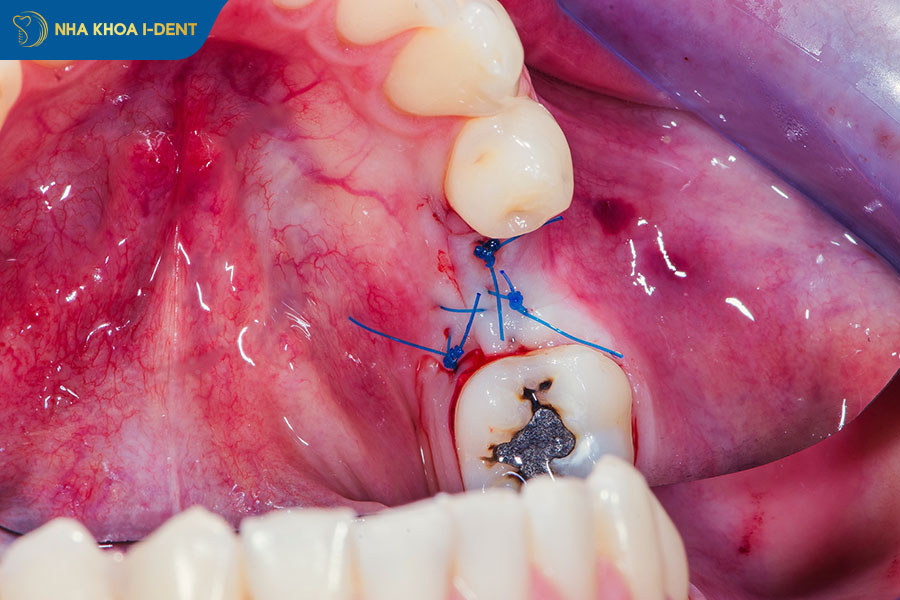

Tuy nhiên, như mọi tiểu phẫu nha khoa, nhổ răng khôn hàm trên vẫn tiềm ẩn một số rủi ro nếu bệnh nhân chọn nha khoa kém uy tín hoặc không tuân thủ hướng dẫn chăm sóc sau nhổ. Dưới đây là các nguy cơ có thể gặp:

- Chảy máu kéo dài: Do bác sĩ thực hiện kỹ thuật nhổ răng sai cách hoặc quá trình chăm sóc không đúng cách sau khi nhổ răng.

- Nhiễm trùng vết thương Nếu dụng cụ nhổ răng không được tiệt trùng kỹ lưỡng, hoặc túi mủ quanh răng không được làm sạch hoàn toàn trong quá trình nhổ, vi khuẩn có thể xâm nhập và gây nhiễm trùng lan rộng